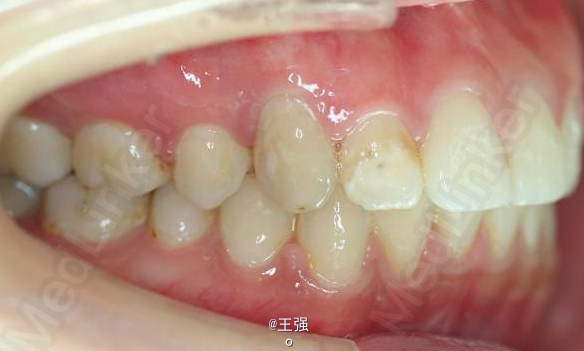

又一例不对称拔牙

牙弓狭窄,牙列拥挤

不对称拔牙